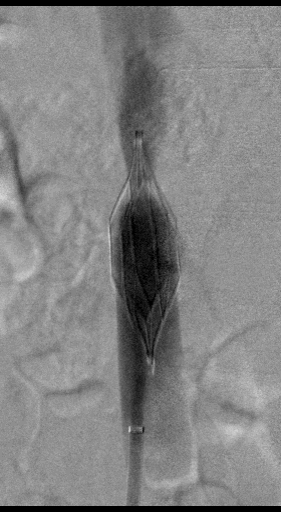

图为:入院后再次尝试腔内回收滤器,经4h努力以失败告终

图为:尝试腔内回收滤器,滤器无法回收入鞘,下腔静脉缩窄明显